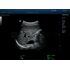

STQ (Sound Touch Quantification)

Sound Touch Quantification (STQ) позволяет быстро в режиме реального времени оценить жесткость ткани печени и определить стадию фиброза.